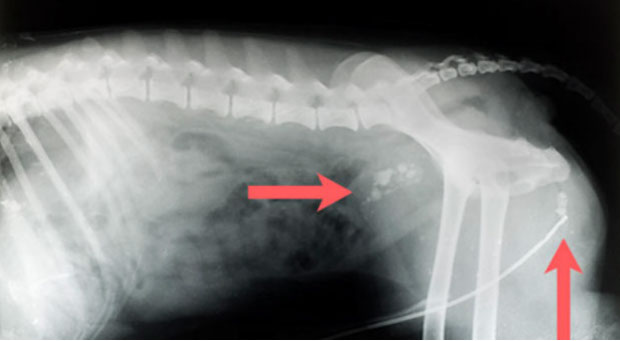

Tumoren in Brust-und Bauchraum (Metastasierung weit fortgeschritten)